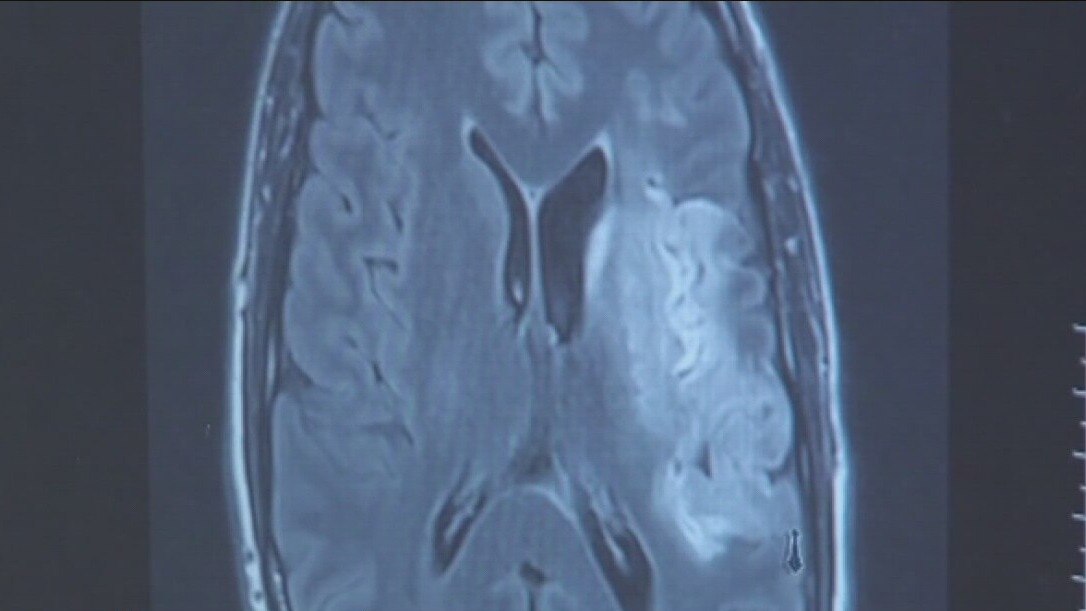

May is National Stroke Awareness Month. When blood flow is cut off from the brain, time is of the essence.